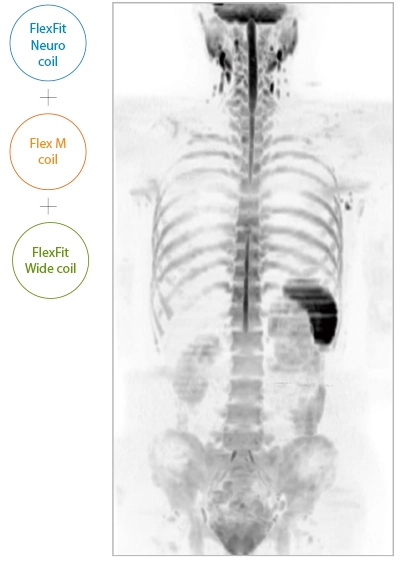

It can also be used with time-consuming scans such as Whole Body DWI and Whole Spine imaging, providing more detailed information in many areas than previously possible.

The ECHELON Synergy ZeroHelium is equipped with a flexible head and neck coil that allows one-action setup via sliding installation, as well as a Flex coil that provides wide and flexible coverage of the imaging area. This enables flexible adaptation to different part of body.